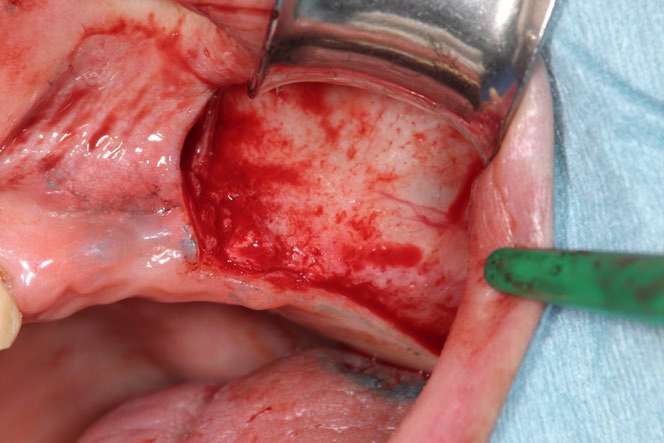

GBR法の手術の流れを写真でご紹介しています。

どのような手術を行うのか、事前に知っていただけたらと思います。

この際に行うのが、上顎洞底挙上術(サイナスリフト)です。

サイナスリフトでは上顎洞側に人工骨の粉末を入れ、上顎洞側に骨の再生を誘導します。

サイナスリフトの手術の流れを写真でご紹介しています。